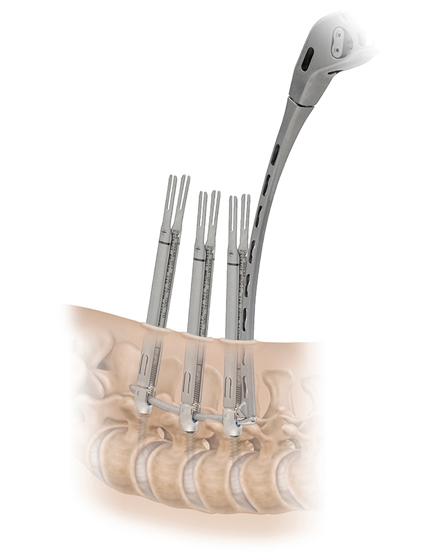

低侵襲脊椎側方固定術 XLIF (エックスリフ)、OLIF(オーリフ)

適応となる疾患:腰椎椎間板ヘルニア、腰部脊柱管狭窄症、腰椎変性すべり症、腰椎変性側弯症など

日本では2013年から承認されている低侵襲な脊椎側方固定術です。この手術は、トレーニングを受けた医師だけが実施できるため、全国でも限られた医療機関でのみ受けられます。当センターの日方医師は資格を有しているため実施可能です。この手術の最大の利点は脊髄神経を直接触らないで神経を圧迫から解除することにあります。側腹部に約5cmの皮膚切開により、下図のように神経機能を電気モニタリングで随時確認し重要な神経を避けながら椎間板内に人工骨を移植します。その後、腰部から固定術を行います。翌日から起立・歩行が許可され、入院期間は通常10~14日程度になります。